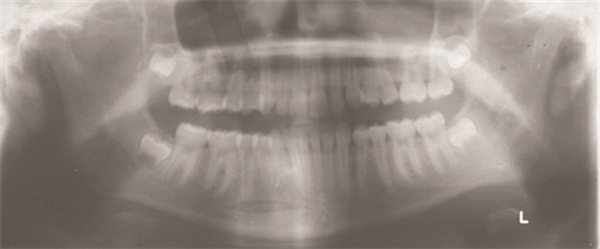

One case posted to the community involved a 13-year-old with a lingually displaced UL3 and plans for full braces, extraction of the primary ULc, and possible exposure and ligation (Figs. 1–5). The treating orthodontist asked: How likely is this canine to correct on its own after extraction?

Fig. 1